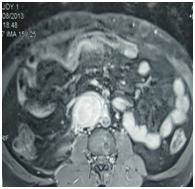

Complete hemogram, liver and renal function tests were within normal limits, normal electrocardiograph and normal chest radiograph. His abdominal x-ray and ultrasound examinations were with no abnormality detected. Urinary 24 hours vanillyl mandelic acid was elevated (18mg/day against 2-8 mg/day). His chest CT was normal. MRI abdomen and pelvis showed a well-defined, heterogeneously enhancing retroperitoneal mass lesion seen beyond the aortic bifurcation at the level of the right common iliac artery abutting the common iliac artery and the IVC with areas of flow voids. Other solid organs normal patient diagnosed extra adrenal pheochromocytoma (paraganglioma). Put on alpha blocker- prazocin 1mg and enalapril 5 mg. Beta blockers were withheld as the patient’s pulse & BP standardized on Alpha blockers itself. Patient was taken up for laparotomy for excision of the tumor. Trans peritoneal approach was followed.

Figure 1 MRI abdomen axial-paraganglioma.